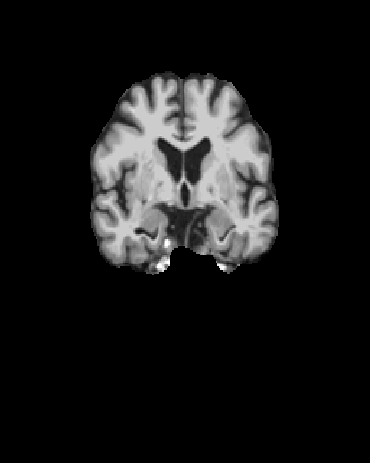

Refer to captionRefer to captionRefer to caption

(a) The axial, coronal, and sagittal view of the “preprocessed” scans.

(b) The axial, coronal, and sagittal view of the FreeSurfer post-processed scans.

(c) The 52nd axial, 92nd coronal, and 58th sagittal view of the brain extraction outputs from Clinica, which we used for 2D classification.

Figure 2: Slices from “preprocessed” scans, FreeSurfer post-processed scans, and the specific slices we use for 2D classification.

Furthermore, we extract 2D slices from fixed indices for each view of the spatially normalized brain extraction output. The indices were chosen based on visual prominence of the hippocampus of the brain. Specifically, they were the 52nd slice of axial view, the 58th slice of sagittal view, and the 92nd slice of coronal view. We also experimented with using neighboring slices for classification. Figure 2 shows the 2D slices of the brain extraction output by Clinica.